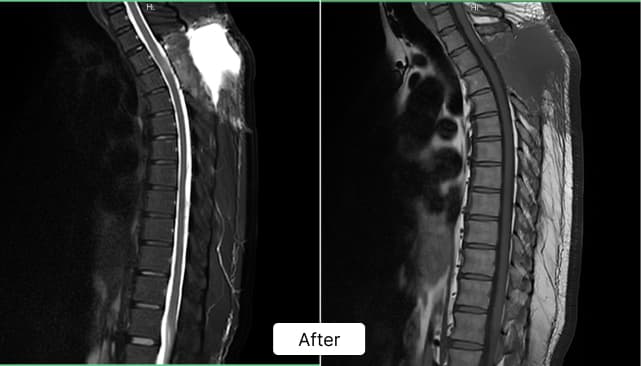

Diagnostic Imaging & Early Diagnosis:

MRI revealed a 22 × 12 × 11 mm tumor at the D2–D3 level, compressing the spinal cord and causing progressive neurological symptoms.

The patient underwent successful spinal tumor removal surgery with precise cord decompression and specialized neurological care.